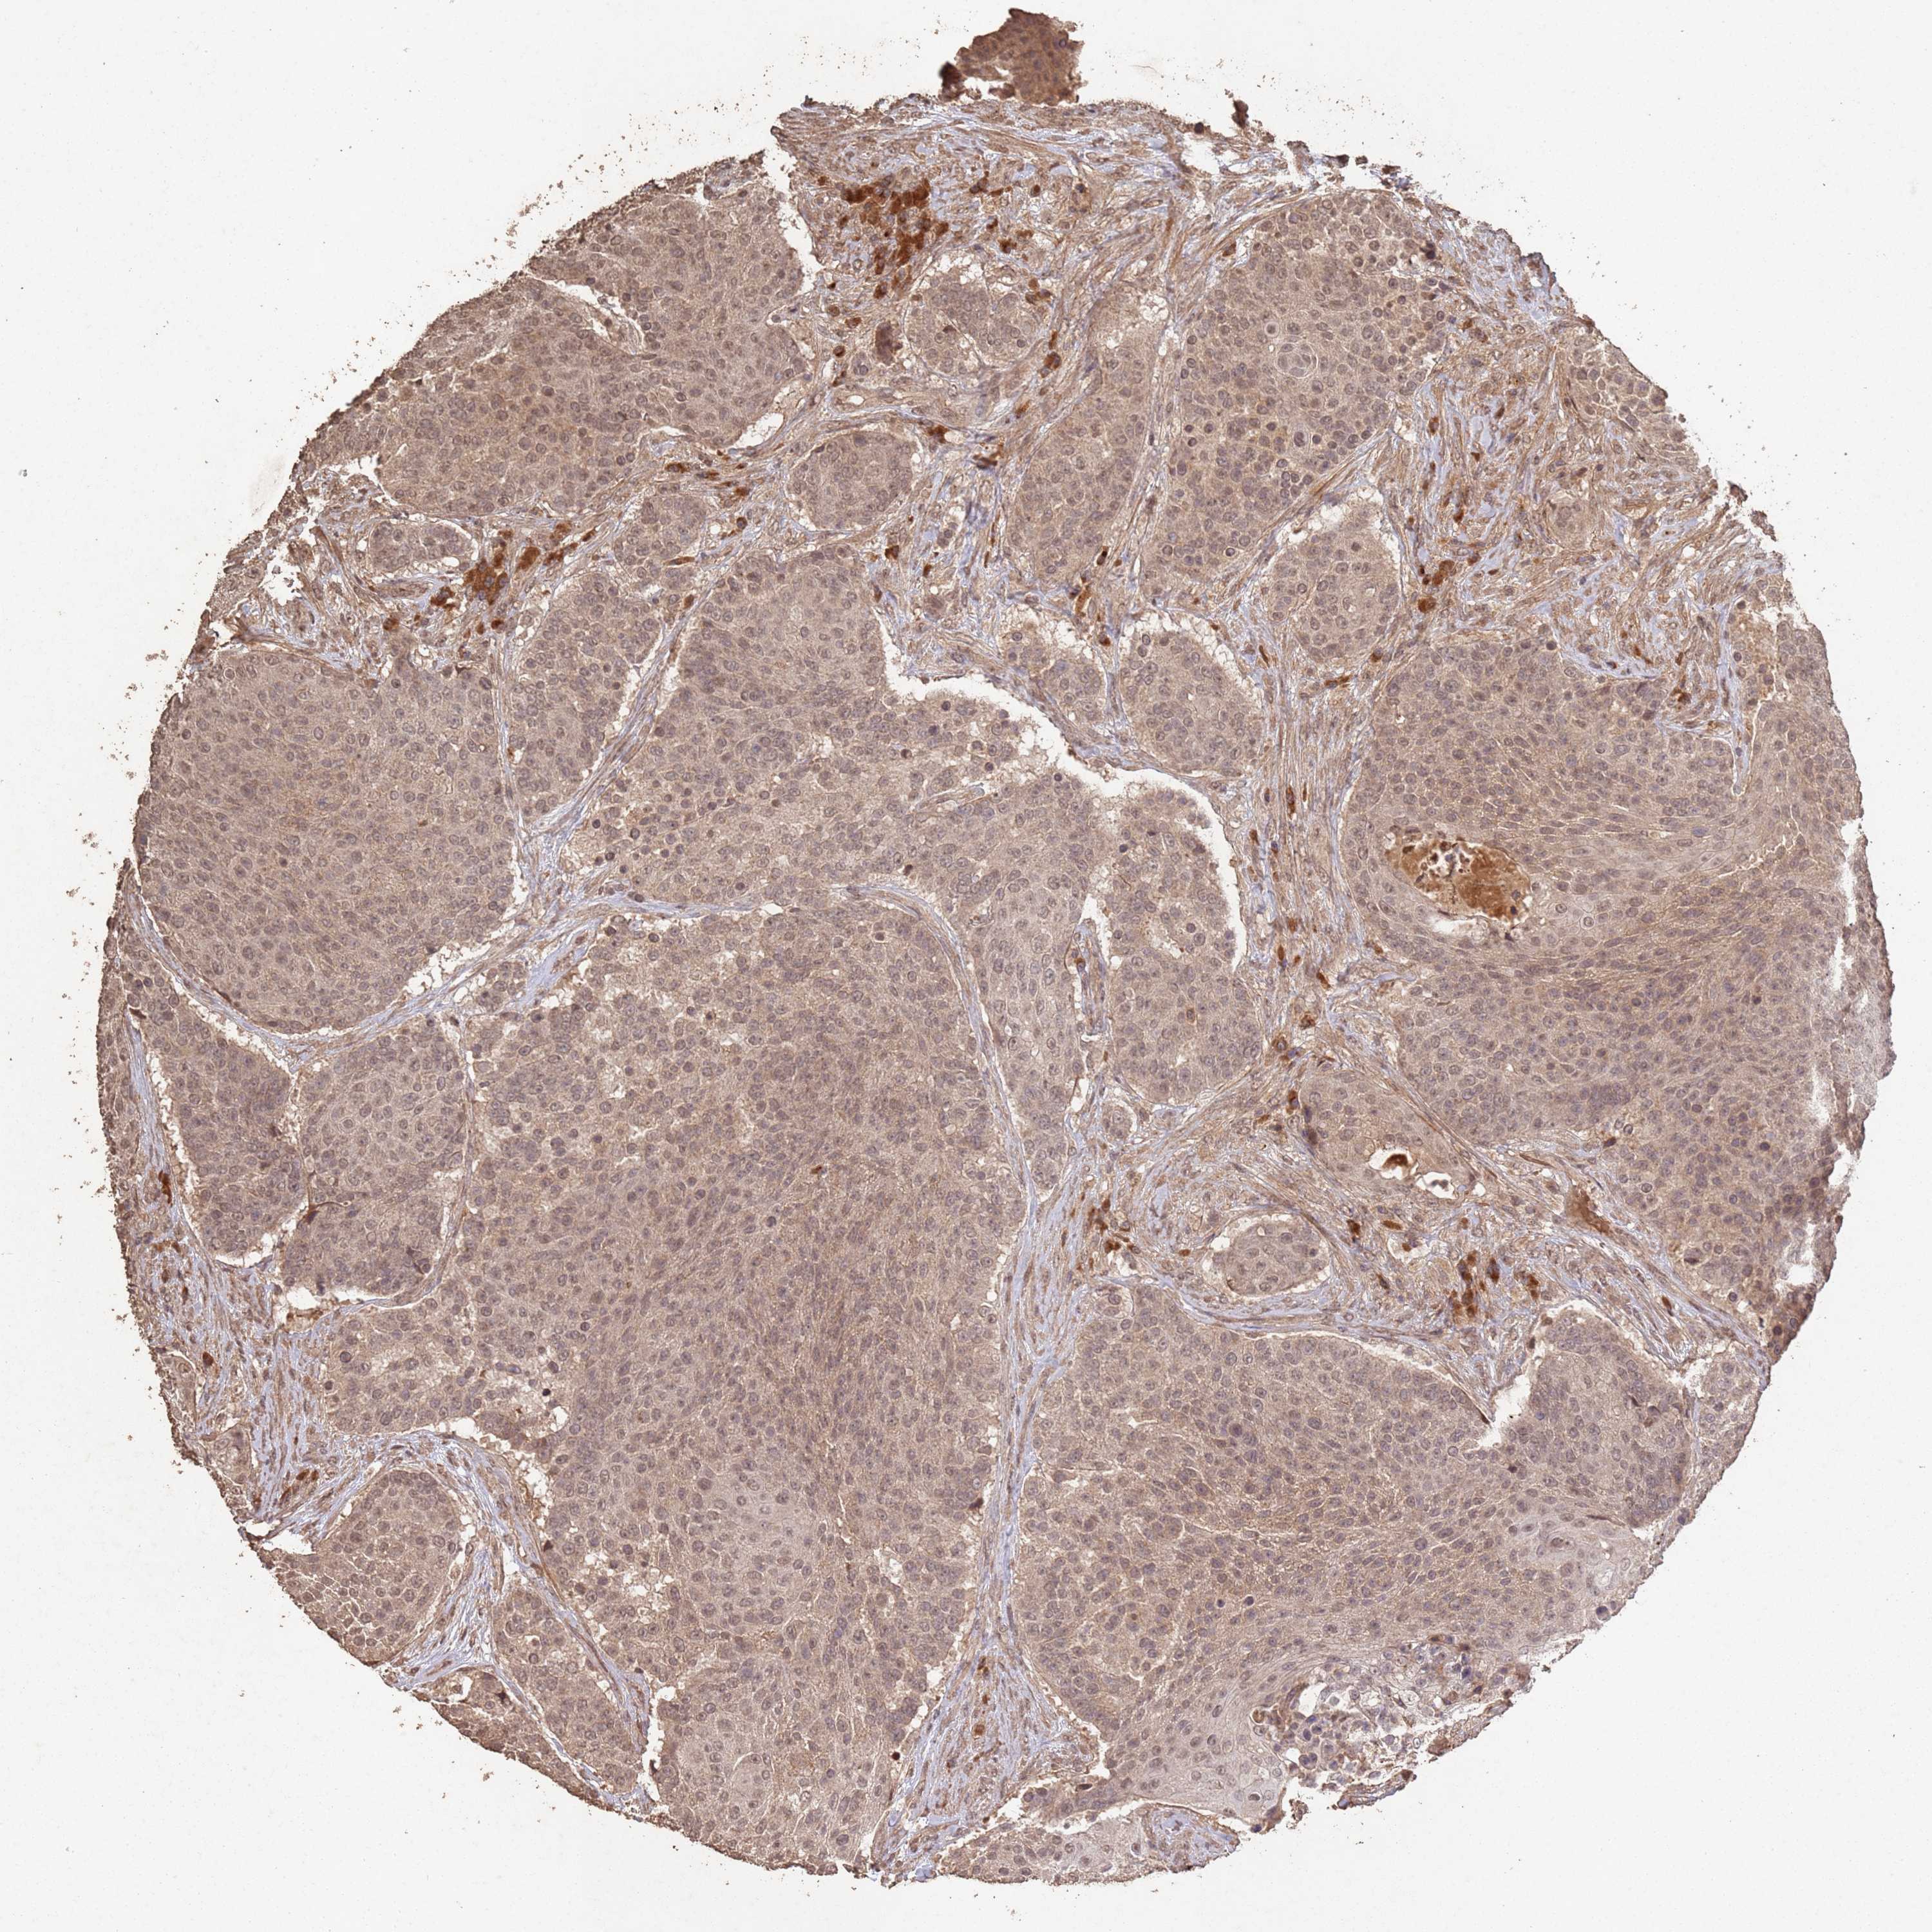

UROTHELIAL CANCER - Protein expressioni

A mouse-over function shows sample information and annotation data. Click on an image to view it in a full screen mode. Samples can be filtered based on level of antibody staining by selecting one or several of the following categories: high, medium, low and not detected. The assay and annotation is described here.

Note that samples used for immunohistochemistry by the Human Protein Atlas do not correspond to samples in the TCGA dataset.

Antibody stainingi

Antibody staining in the annotated cell types in the current human tissue is reported as not detected, low, medium, or high, based on conventional immunohistochemistry profiling in selected tissues. This score is based on the combination of the staining intensity and fraction of stained cells.

Each image is clickable and will lead to virtual microscopy that enables deeper exploration of all samples and also displays staining intensity scores, fraction scores and subcellular localization as well as patient and tissue information for each sample.

Antibody CAB046472

Staining

High

Medium

Low

Not detected

Intensity

Strong

Moderate

Weak

Negative

Quantity

>75%

75%-25%

<25%

None

Location

Nuclear

Cytoplasmic/membranous

Cytoplasmic/membranous,nuclear

Urothelial carcinoma, High grade

Urothelial carcinoma, Low grade